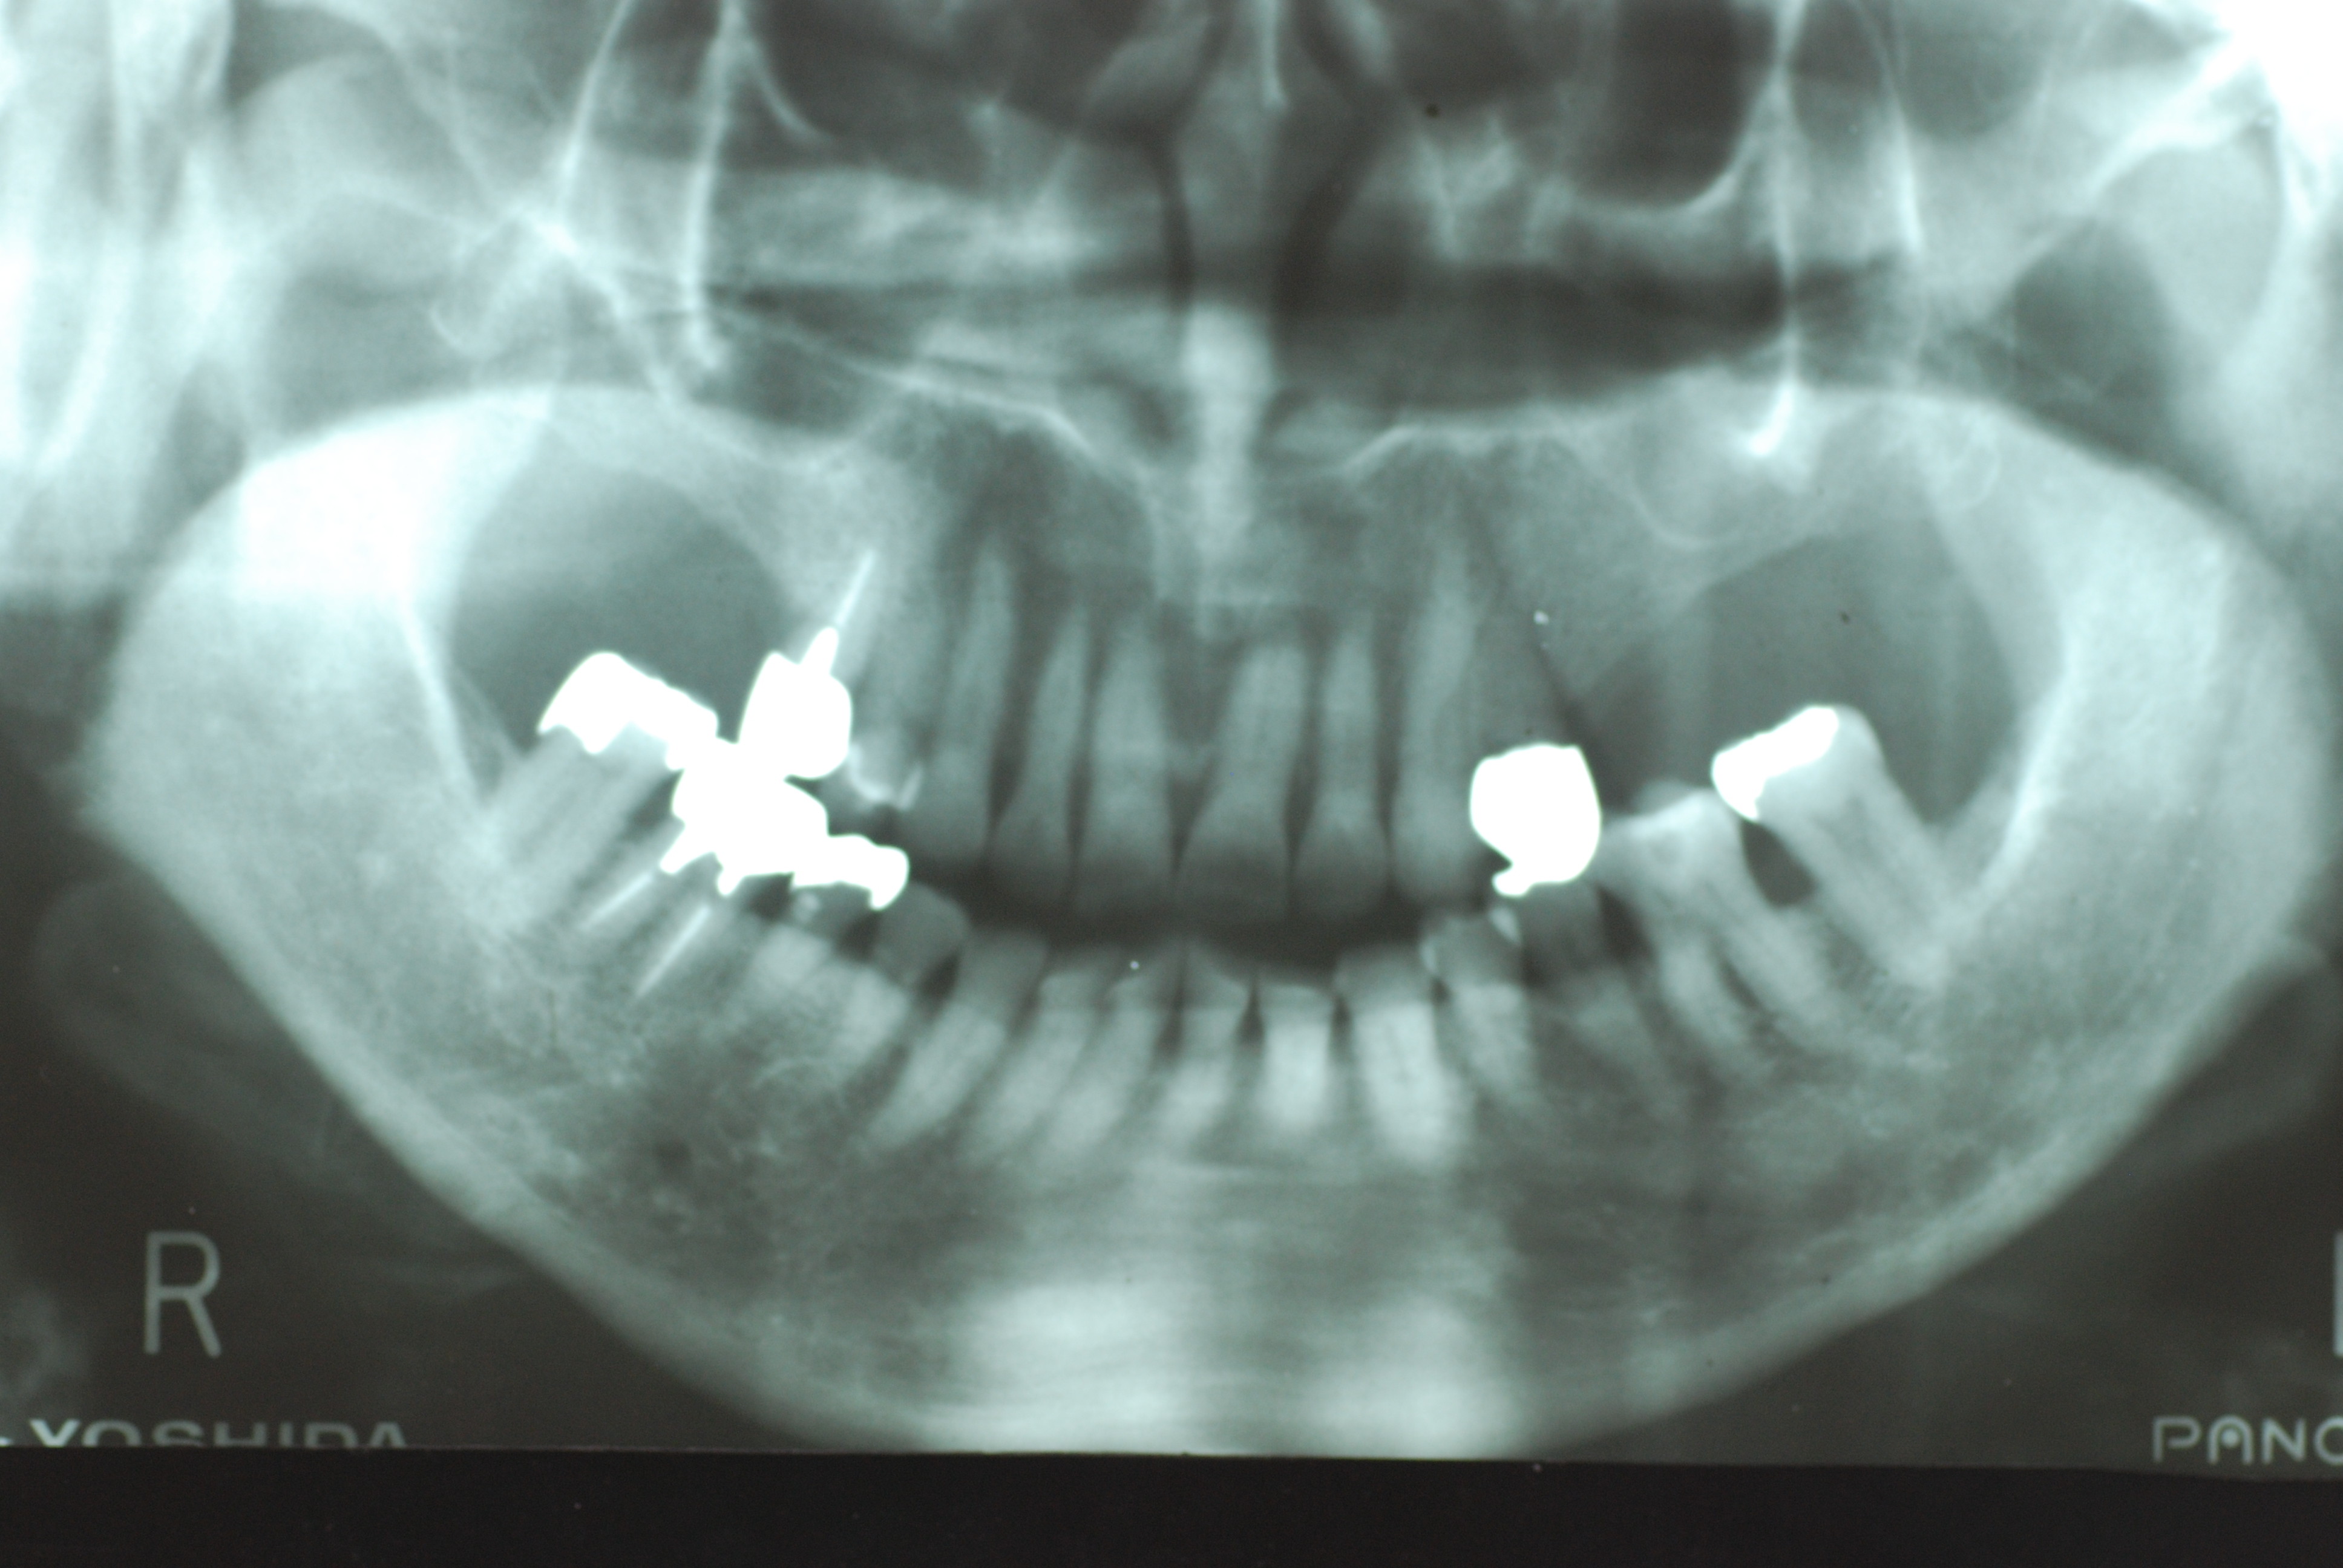

数年経過した上の歯です。折れた歯は差し歯になっています。その隣の

白い歯が差し歯にしていない歯です。神経はありません。

下の歯も一見解らないでしょう。

差し歯にするのは避けたいところです。折れたりしたら仕方ないことですが、以外と折れずにすむこともあるのです。

ただ、あちこちにまだ歯茎の炎症があり、歯の間も沢山虫歯なのです。